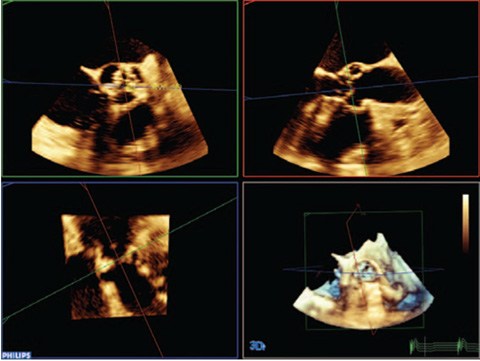

L’intelligence anatomique appliquée à l’échographie utilise la modélisation avancée des organes, la fonction de découpe des images et des outils de quantification éprouvés. Les examens sont ainsi plus faciles à réaliser, davantage reproductibles et plus riches en informations, ce qui permet de relever les défis cliniques et économiques des environnements médicaux actuels. L’intelligence anatomique est utilisée dans les solutions d’imagerie Philips telles qu’EchoNavigator, EP navigator et HeartNavigator. Aujourd’hui, elle fournit déjà aux cliniciens des outils de traitement sophistiqués mais faciles à utiliser. En outre, elle leur permet d’identifier rapidement et plus précisément une anatomie et des anomalies, d’évaluer le stade des maladies, de décider du traitement et de guider les interventions.

L’intelligence anatomique étudie les données échographiques d’un patient et applique une intelligence adaptative du système à l’aide de modèles anatomiques en 3D, pour obtenir plus facilement des résultats davantage reproductibles.

Découvrez HeartModelᴬ⋅ᴵ⋅, une nouvelle application d’intelligence anatomique appliquée à l’échographie (AIUS) intégrant les fonctionnalités suivantes pour l’échocardiographie : quantification 3D temps réel, affichages 2D automatisés et reproductibilité performante. HeartModelᴬ⋅ᴵ⋅ détecte, segmente et quantifie automatiquement l’oreillette gauche et le ventricule gauche à partir d’un volume 3D.